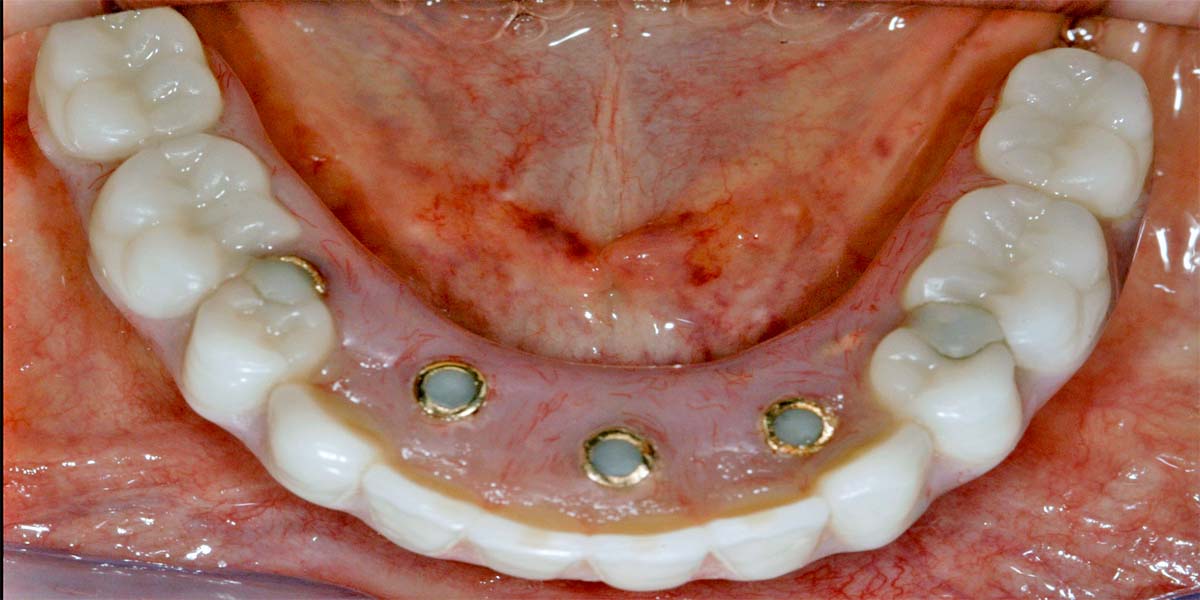

Milyen problémák lehetnek a fogászati implantátumokkal? A fogászati implantátum évtizedek óta a legígéretesebb, a természeteshez leginkább hasonló, megjelenésben és funkcionalitásban tökéletes fogpótlás, rendkívüli életminőség javító előnyökkel. Mivel a fogászati implantátum a természetes foggyökérhez hasonlóan a fog- vagy az állcsontba van beültetve, annak mintegy részévé válik. Így képes arra, hogy nagy